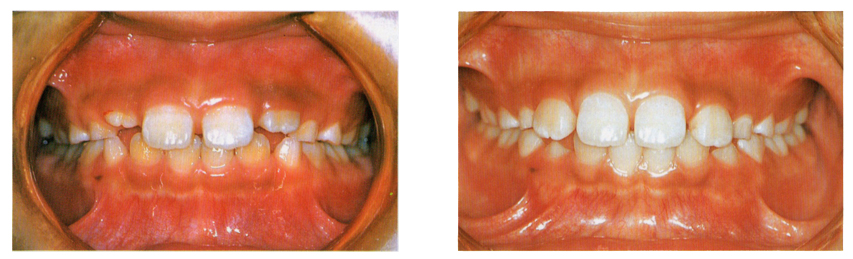

・ 7〜8歳ごろの小児の口の中

5歳くらいから下の前歯がだんだん永久歯に交換してきます。

下の歯は乳歯の裏側から生えてくることが多く、自然に前に出で来るのが普通です。また、上の前歯の真ん中は写真のように

一時的に隙間が開いた感じになりますが、隣の歯が生えてくるのにつれて隙間がふさがってくるのが普通です。

ただ、ただ将来において歯並びなどの問題に影響する場合がありますので、歯科医院での診断と定期的な観察が必要です。

また、不自然な生え方をしてきた永久歯があれば、歯科医院を受診して悪影響がないように処置してもらうようにしてください。

・ 11歳ごろの小児の口の中

12歳くらいで乳歯はほとんど永久歯と交換していきます。写真は上下左右に1本ずつ、4本の乳歯が残った状態です。

奥から2本目の歯が乳歯なのですが結構大きな歯なので永久歯とお間違えになる方もいらっしゃいます。

この写真の一番奥の歯は6歳臼歯になります。

・ 13歳ごろの小児の口の中

乳歯がすべて抜けて永久歯に交換しました。6歳臼歯の奥に12歳臼歯が生えています。

上下それぞれに14本、合わせて28本の永久歯が生えています。